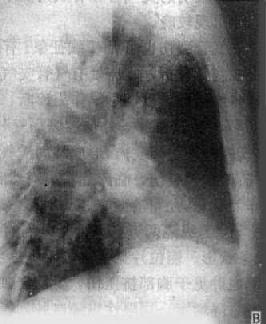

图3-1-24 右肺中心型肺癌伴肺门淋巴结转移

A.后前位 B.右侧位 C.侧位体层像

右肺门区可见圆形肿块影,边界清楚

体层摄影示肿块影边界不规则(→),

并见增大淋巴结向支气管突入